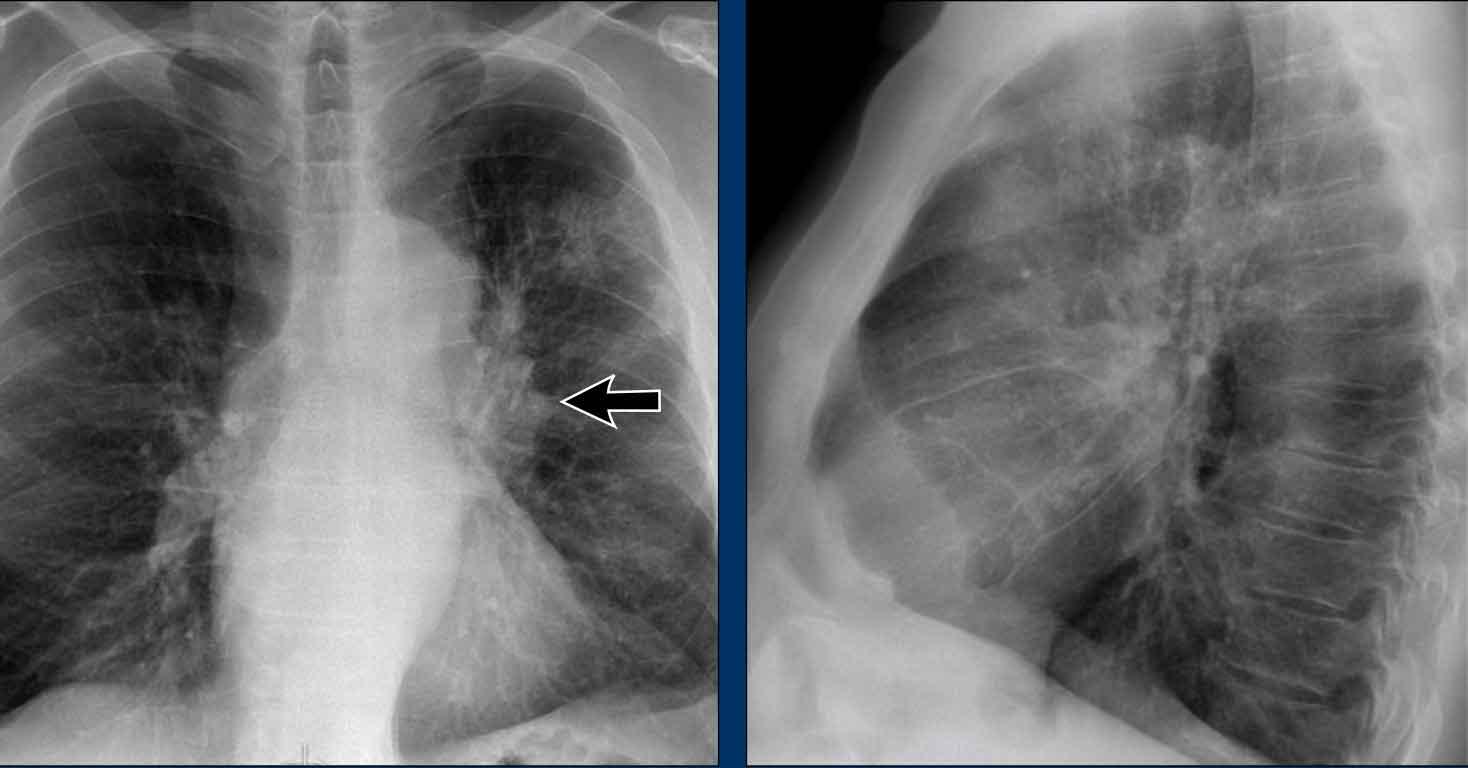

To rốn phổi – ca 1

Trong trường hợp này, bóng rốn phổi to ra ở cả hai bên. Nguyên nhân có thể do mạch máu giãn to hoặc hạch bạch huyết to. Một dấu hiệu rất có giá trị trong trường hợp này là khối nằm bên phải khí quản.

Đây được gọi là dấu hiệu 1-2-3 trong bệnh sarcoidosis, tức là to rốn phổi trái, rốn phổi phải và hạch cạnh khí quản.

Dưới đây là thêm một số ví dụ về bệnh sarcoidosis.

Nhấp vào hình để phóng to.

- Hạch bạch huyết to và hình ảnh kính mờ (ground-glass) ở phổi

- Hạch bạch huyết to, dấu hiệu 1-2-3

- Hạch bạch huyết to khối lớn

- Dấu hiệu 1-2-3

- Hình ảnh nốt ở phổi, không có hạch bạch huyết to

- Hạch bạch huyết rốn phổi và cạnh khí quản to